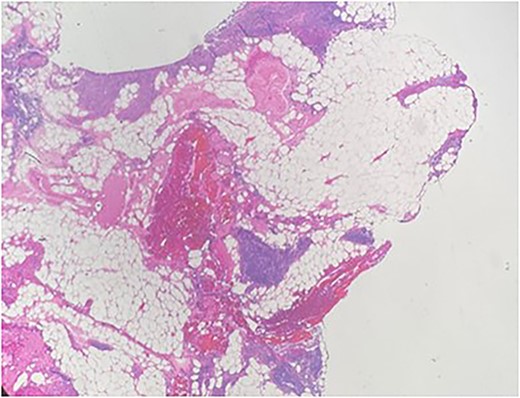

A 36-year-old male with a history of end-stage renal disease (because of polycystic kidney disease) on dialysis, for which he is on paricalcitol and sevelamer, and total parathyroidectomy with autotransplantation in the left forearm performed in 2011 for secondary hyperparathyroidism presented with generalized bone pain. Heart rate was 114 bpm, respiratory rate was 18 breaths/min, oxygen saturation was 96% and blood pressure was 136/72 mmHg. Laboratory investigations were ordered and revealed high PTH (>1300 pg per ml), low calcium (2.7 mg per dl) and low phosphate (1.8 mg per dl). A sestamibi scan was ordered and revealed hyperactive parathyroid tissue in the upper retrosternal area (Fig. 1). Removal of the ectopic parathyroid tissue was planned; however, the lesion was not localizable intraoperatively, and further chest CT with preoperative coil localization was performed, which revealed a retrosternal ectopic parathyroid tissue anterior to the ascending aorta (Fig. 2).Right thoracoscopy using fluoroscopy for ectopic parathyroid removal and lymph node biopsy was performed, and the specimens were sent to histopathology, which showed multiple nodules of parathyroid tissue with benign lymph nodes (Figs 3 and 4). A final diagnosis of parathyromatosis was made. The patient was discharged in good condition without complaints of bone pain. Upon 2-week follow-up, the patient was symptom-free and laboratory investigations revealed phosphate of 2.1 mg per dl, calcium of 2.4 mg per dl and an elevated PTH of 350 pg per ml, for which a sestamibi scan was performed and showed no evidence of uptake in the neck and mediastinum but revealed uptake in the left forearm from the previous autotransplantation.

Multiple nodules of hypercellular parathyroid tissue within unremarkable thymic tissue.